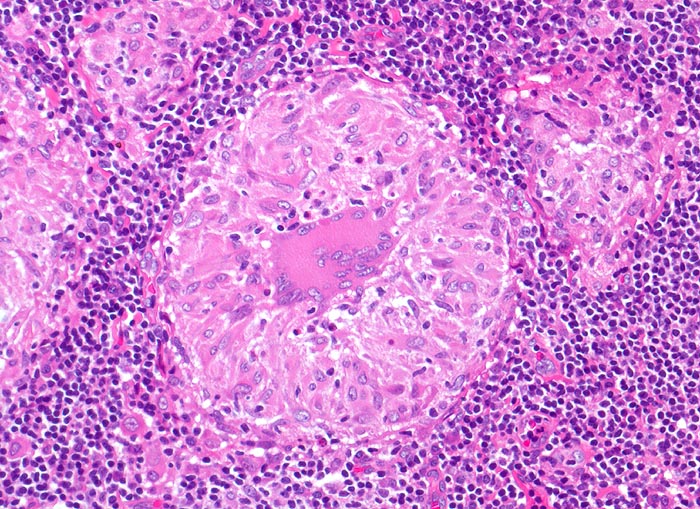

Sarkoidosegranulome bestehen aus Epitheloidzellen mit einem peripheren Lymphozytensaum. Mehrkernige Riesenzellen, meistens solche vom Langhans-Typ mit hufeisenförmig angeordneten Kernen und Asteroidkörperchen (> 4173) können zusätzlich vorhanden sein. Diese Granulome enthalten meist keine Nekroseherde (=produktives Granulom). Man findet diesen Granulomtyp hauptsächlich in Lymphknoten, aber auch in inneren Organen und in der Haut. Die Sarkoidosegranulome zeigen in späteren Stadien eine charakteristische perigranulomatöse und die Granulome septierend unterteilende Fibrose (> 4015).

Morphologische Merkmale:

• Wenig erhaltenes Lymphknotengewebe (blau).

• Konfluierende Granulome aus grossleibigen Epitheloidzellen.

• Wenige mehrkernige Riesenzellen.

• Kleinere Nekroseareale im Zentrum grösserer Granulome. (Die Nekrosen sind untypisch für die Sarkoidose, können aber bei grossen Granulomen gelegentlich vorkommen).

• Perigranulomatöse Fibrose. Das sollte der Kliniker dem Pathologen mitteilen: